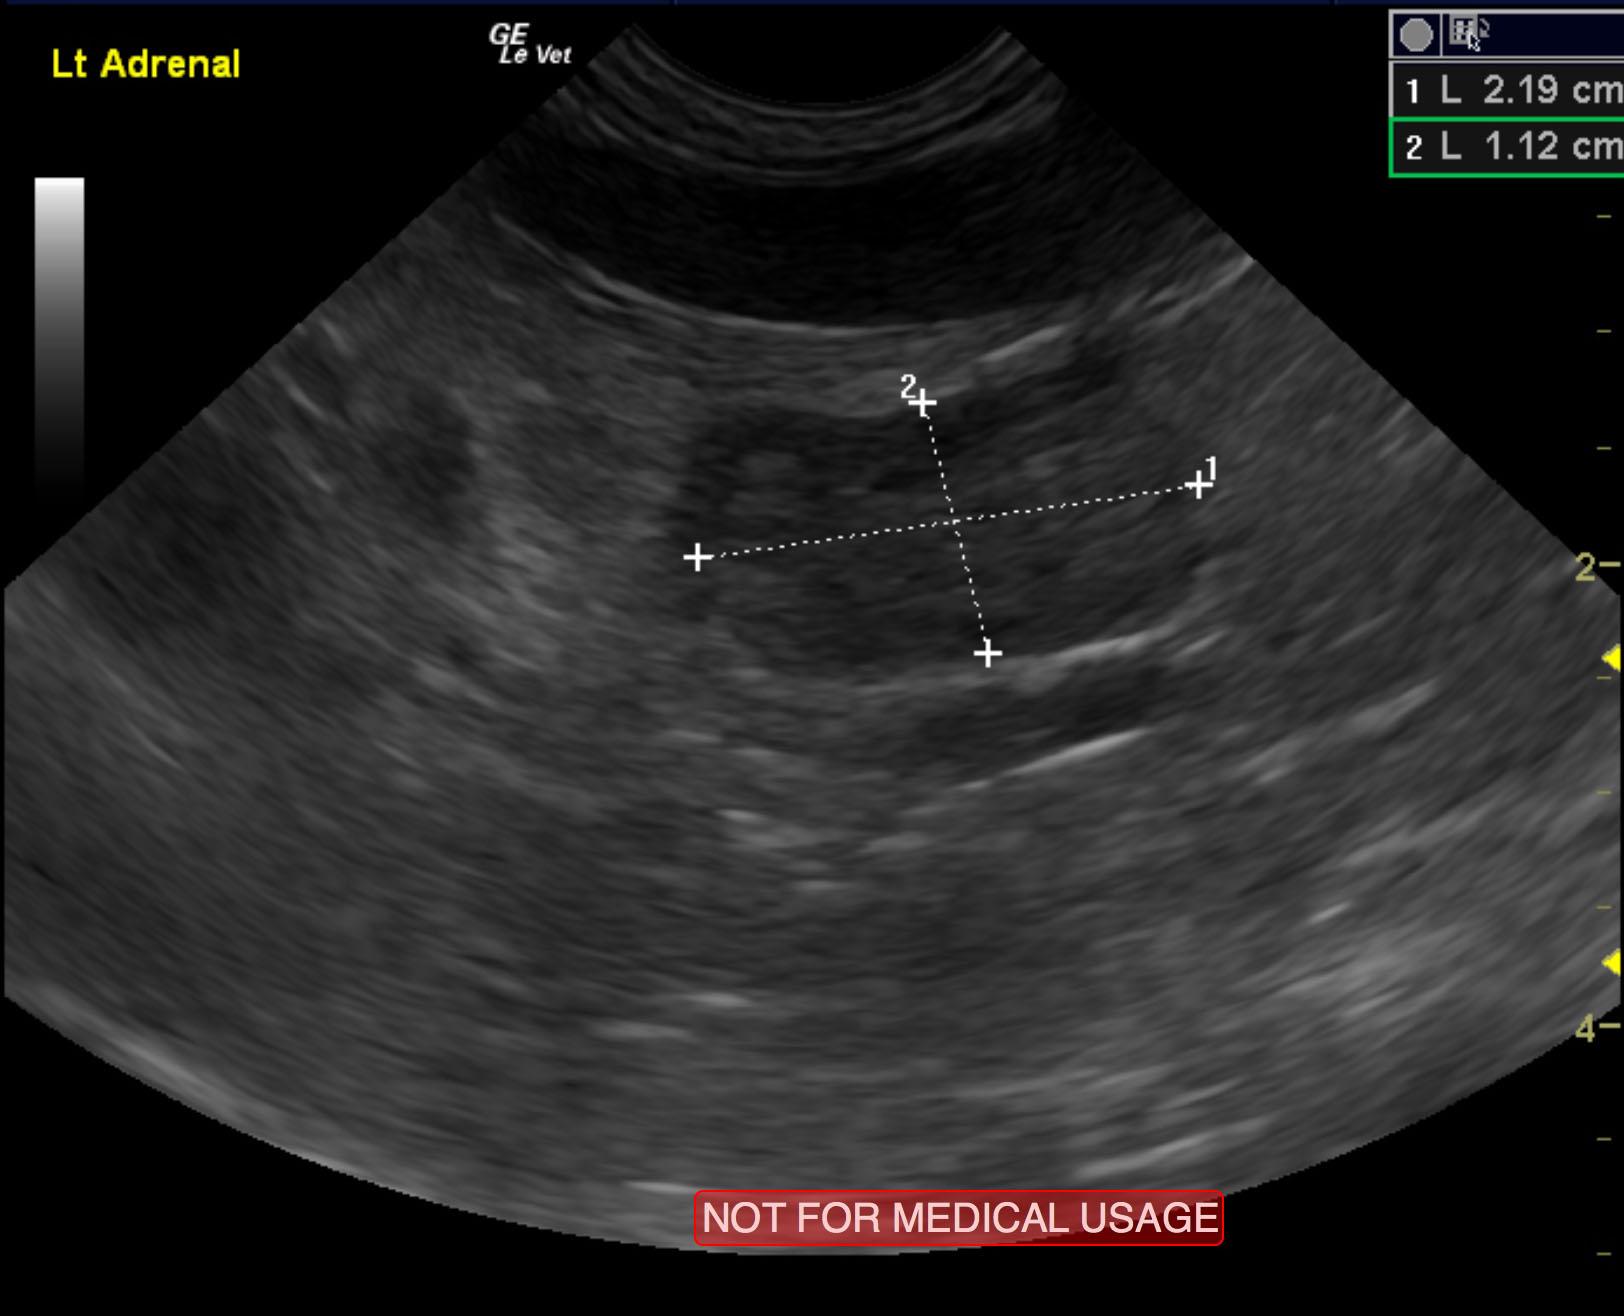

Left adrenal gland mass. Suspect carcinoma. This appears surgically resectable. Lymphadenopathy involving epigastric, splenic and portal lymph nodes. These are likely related given the contiguous pattern of associated vasculature between the spleen, gastrointestinal tract and liver in the portal system.

The left adrenal gland comprised a mass that measured 2.2 x 1.12 cm. Capsular expansion was noted at the caudal pole with pericapsular inflammatory pattern. It appeared significantly vascular with a trace amount of free fluid noted adjacent to it. This suggests a fairly aggressive process, but there was no evidence of vascular invasion noted. The right adrenal gland was uniform and measured 0.72 x 0.32 cm. Lymph node enlargement was noted in the epigastric region and measured 1.02 x 0.82 cm. A separate lymph node medial to the spleen was also enlarged, measuring 1 x 0.82 cm.

Ultrasound guided FNA of the left adrenal gland was performed, and results were consistent with adrenocortical neoplasia. FNA of the lymph nodes were also performed, and cytology revealed heterogenous, lymphoid population, no evidence of metastasis.